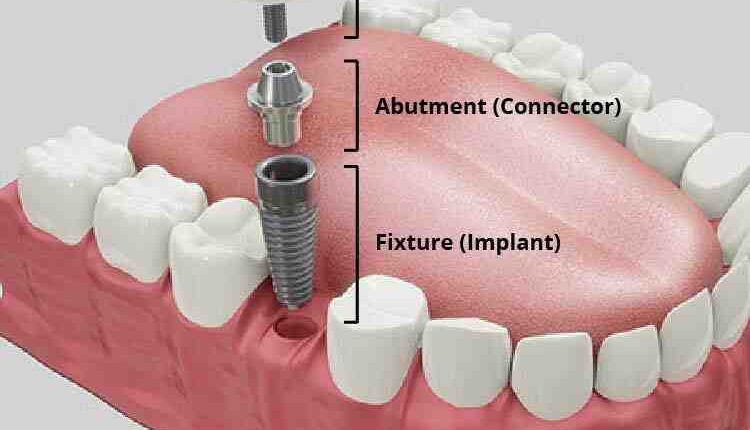

How Much Does a Dental Upgrade Cost? The average cost of implant dental implants is $ 3,000 – $ 5,000. Includes post, abutment, and crown placement. Bone marrow transplants, dental extractions, CT scans, and X-rays are performed separately.

Basically, there are three different service providers of dental implants, which include dentists (general or cosmetic), surgeons and time sellers.